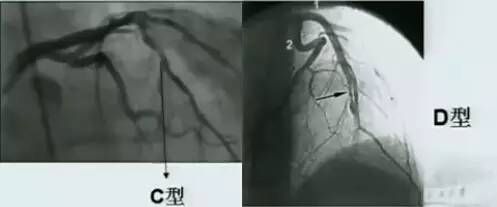

(2)夹层分型

A型:造影剂无滞留,冠脉腔内出现局限线性透光区。

B型:冠脉腔内出现与血管平行的条状显影。

C型:血管壁外造影剂滞留。

D型:螺旋夹层。

图7 动脉夹层C型(左)和D型(右)